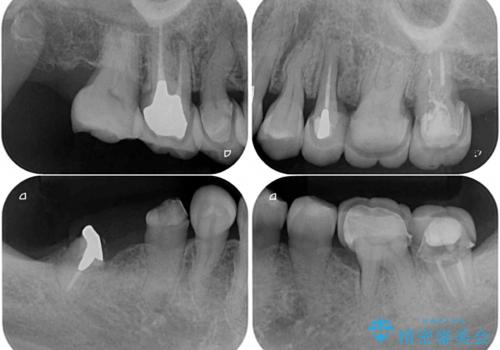

- 治療をおこなって以来、クラウン周りの歯肉から出血が続くとのことで来院された患者様です。

診察を行ったところ、クラウンと歯の境目が不適合で汚れが溜まりやすく、炎症を起こしている状態でした。

治療を終えたばかりですが、出血を改善するためには作り直しが必要と判断し、オールセラミッククラウンにて補綴治療することとしました。

他にも、咬合時に痛みを感じる歯や、欠損により咬みにくい奥歯などをインプラントを用いて治療を行うこととしました。

右下は、残存歯の状態があまり良くなかったため、今後抜歯となったことを想定して、最後臼歯のインプラントを決定しました。